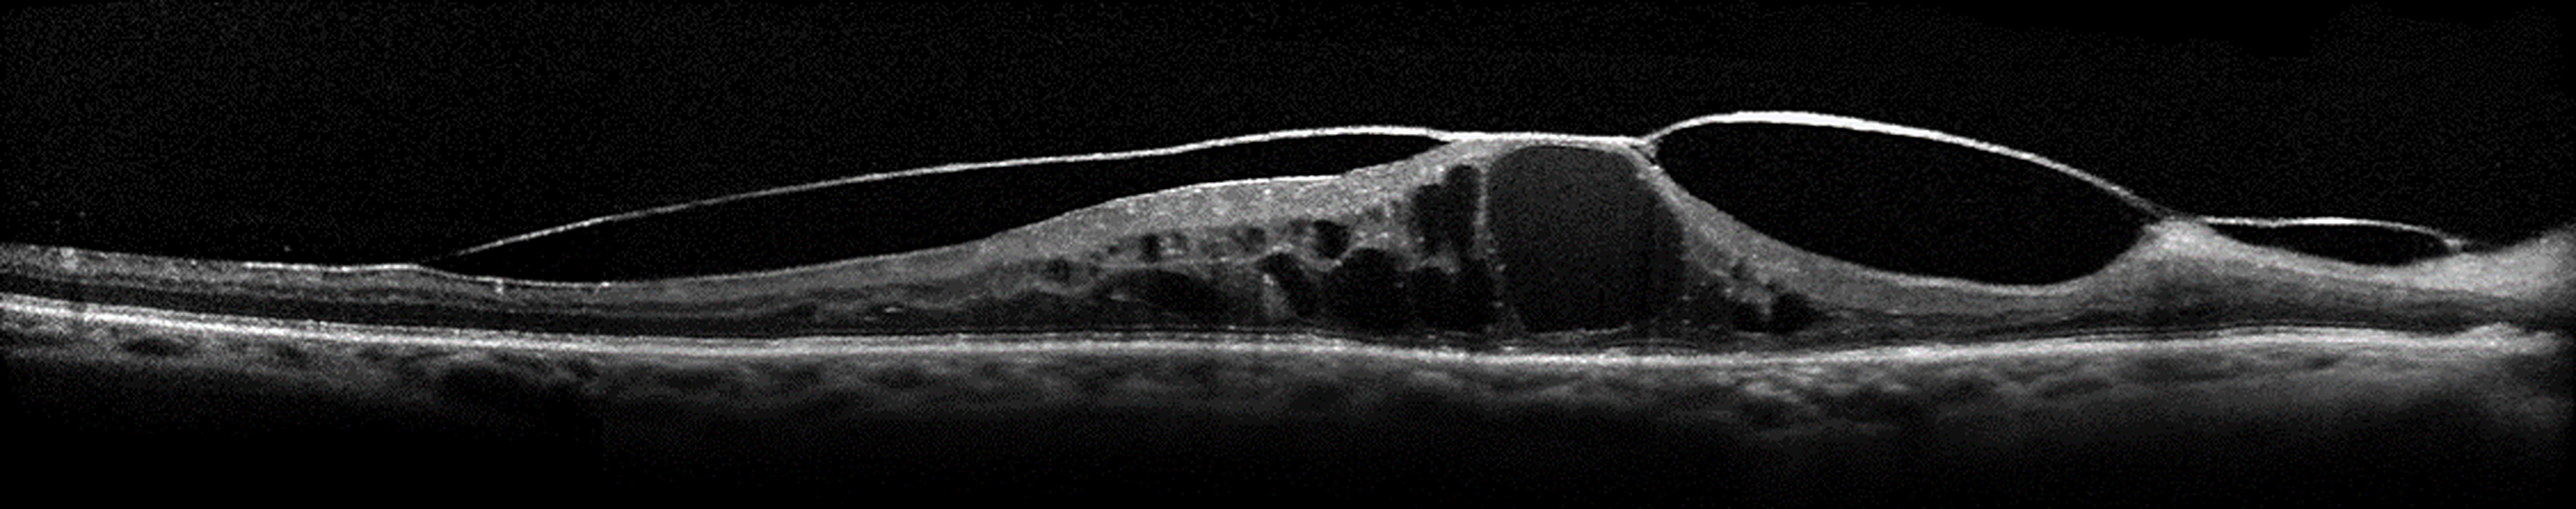

Traitements actuels de l’œdème maculaire diabétique et indications chirurgicales dans la rétinopathie diabétique

La rétinopathie diabétique est une affection fréquente touchant une population jeune et active.

Dans ce contexte, il est nécessaire de pouvoir identifier les signes cliniques d’un œdème maculaire diabétique OMD ou les indications chirurgicales afin d’assurer une bonne prise en charge du patient diabétique.